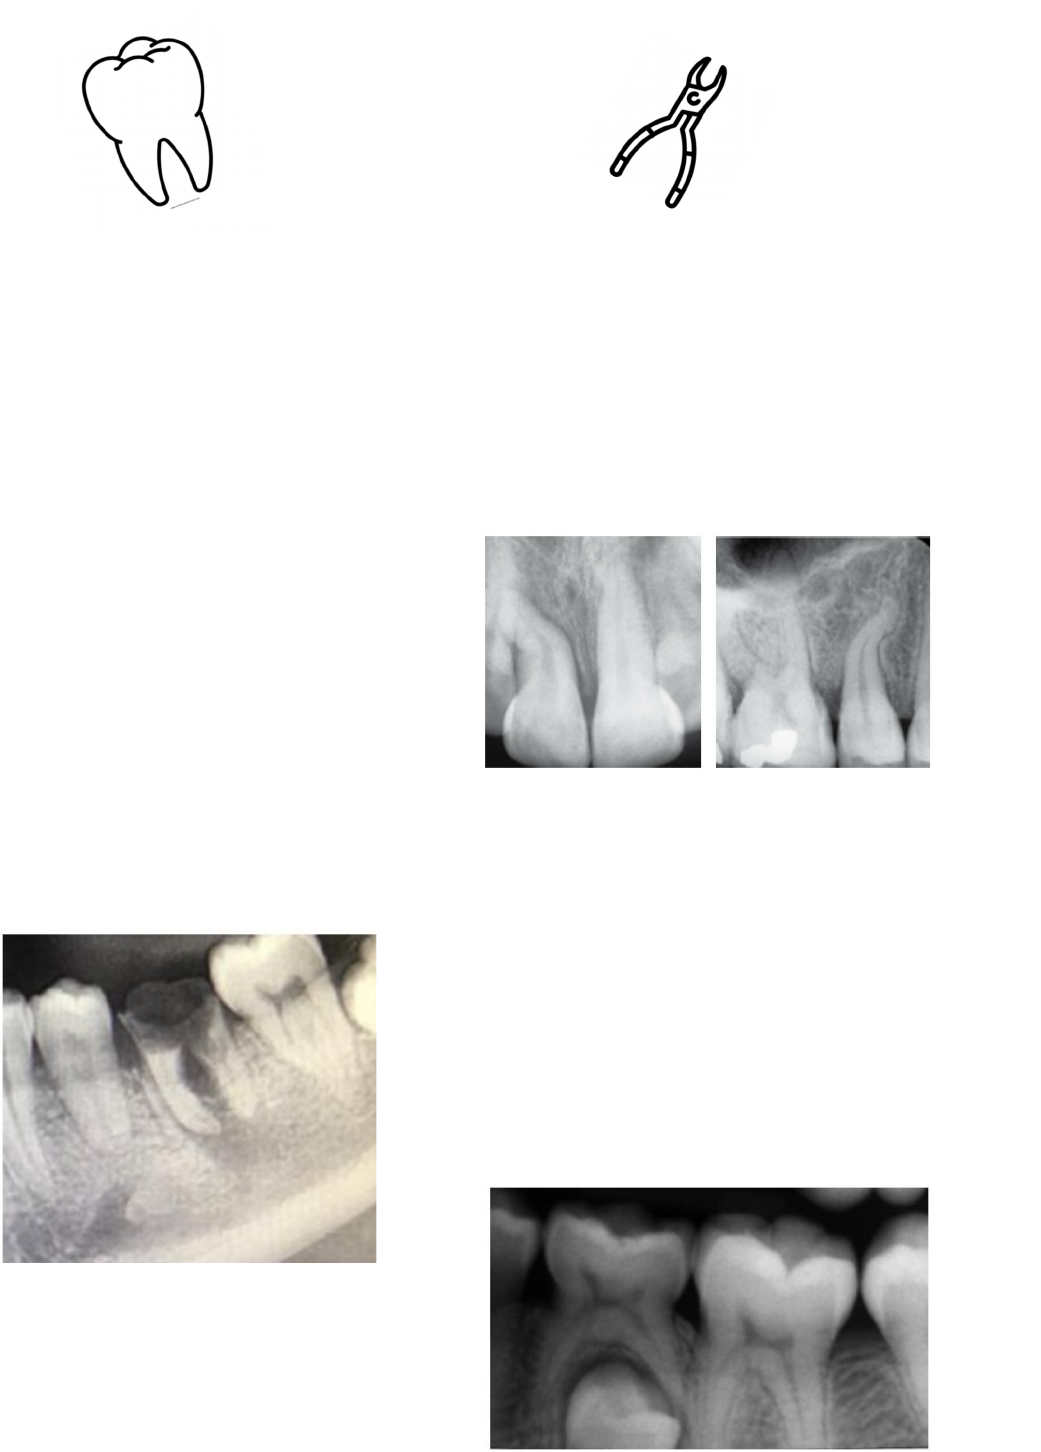

Dentes com amplas destruições coronárias, dilacerações apicais e anquiloses poderão ter abordagens muito parecidas. Estes dentes são grandes candidatos à extração aberta..

Primeiro molar com ampla destruição coronária por cárie.

Dentes com dilacerações apicais.

2º molar decíduos anquilosado